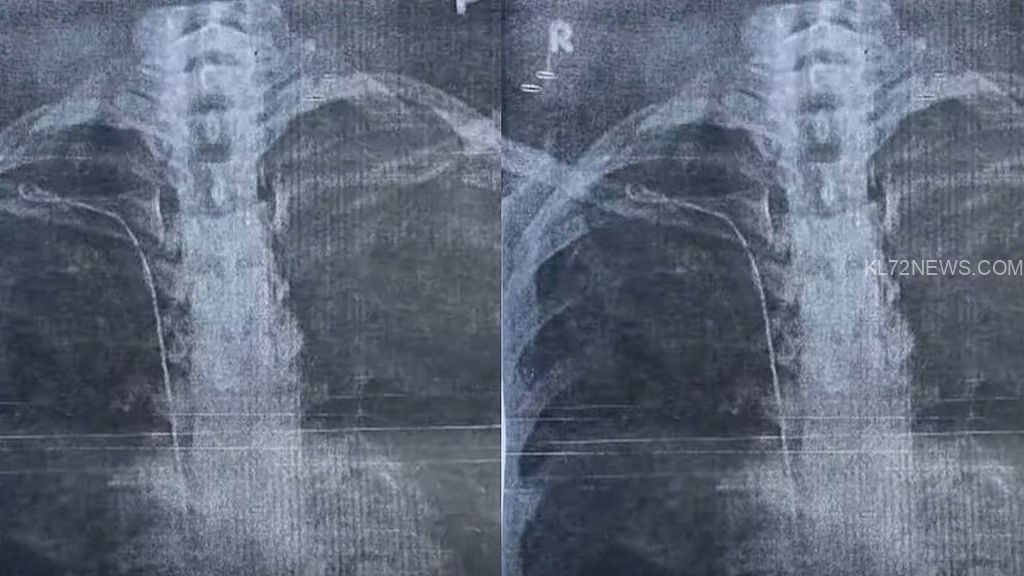

2023 മാര്ച്ച് 22ന് നടന്ന തൈറോയ്ഡ് ശസ്ത്രക്രിയയ്ക്കിടെയാണ് ട്യൂബ് കുടുങ്ങിയതെന്നാണ് യുവതിയുടെ പരാതിയില് പറയുന്നത്. ശ്വാസം മുട്ടലിനെ തുടര്ന്ന് നടത്തിയ പരിശോധനയിലാണ് നെഞ്ചില് ട്യൂബ് കിടക്കുന്നതായി അറിഞ്ഞതെന്നും യുവതി പറയുന്നു. എക്സ്റേയില് നിന്നാണ് സംഭവം അറിയുന്നത്. മരുന്നിനുള്ള ട്യൂബിട്ടവരാണ് ഉത്തരവാദികളെന്നും ഡോക്ടര് ചൂണ്ടിക്കാട്ടുന്നു. ശ്രീചിത്രയില് നടത്തിയ പരിശോധനയിലാണ് ഗൈഡ് വയറാണെന്ന് മനസിലാകുന്നത്.